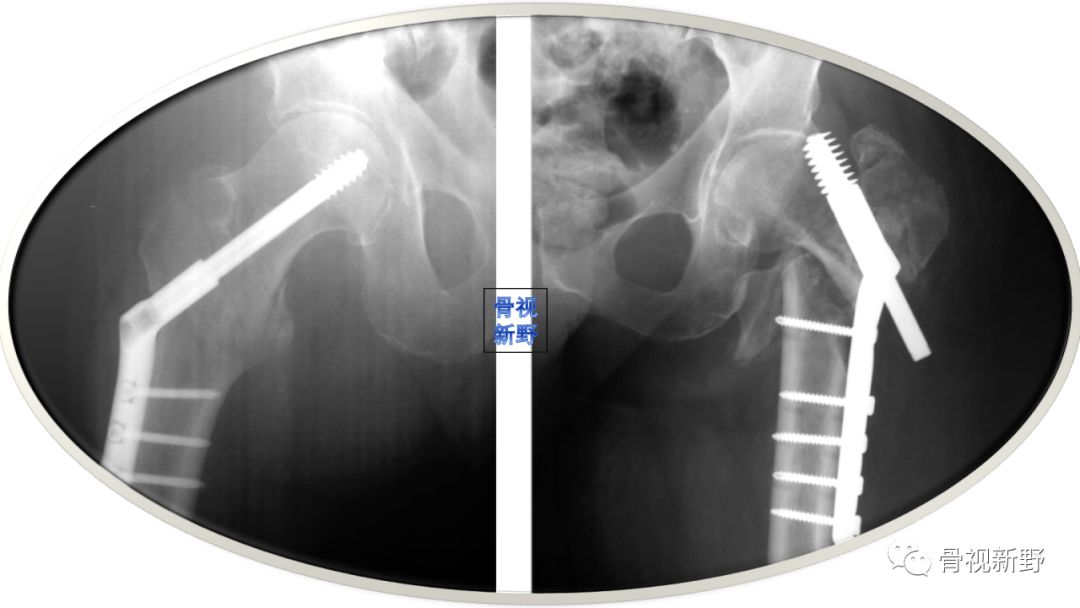

“没有外侧壁,就没有髋螺钉”

累及外侧壁的股骨近端骨折,如反转子及经转子骨折,如果使用滑动髋螺钉,由于缺乏外侧壁的骨性支撑,会发生股骨干向内侧移位及股骨近端骨块向外侧移位。这种移位会导致畸形、骨不连、头钉切出(cutout)。

文献报道反转子骨折用滑动髋螺钉固定的失败率高达56%[Haidukewych GJ 2001]。虽然股骨近端锁定钢板(proximal femoral locking plate,PFLP)、95°角的DCS也可使用,充当外侧皮质的假体,但对更复杂的股骨近端骨折,这些钉板系统并不适合。对反转自骨折,髓内钉较DCS有优势;但髓内钉与PFLP的优、劣对比尚有争议。